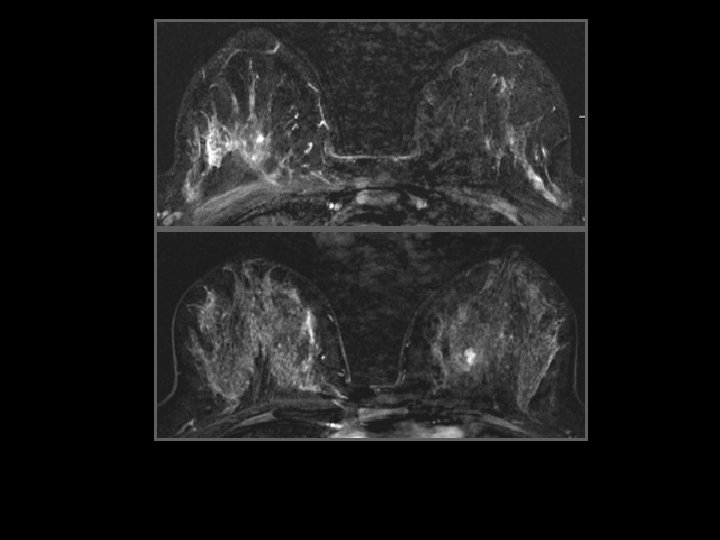

D face ext 46 ans, placard QSE droit de 4 cm palpé par la gynécologue

U Q Sup droits Biopsie : CLI

Carcinome lobulaire infiltrant • 32 cas. Modification de la stratégie thérapeutique 16 fois (50 %) en montrant une tumeur plus extensive que la radiologie conventionnelle Weinstein S et al. MR Imaging of the breast in patients with invasive lobular carcinoma. AJR 2001, 176: 399 -406

• Bilan d'extension locale – Détection de lésions additionnelles : 10 - 50% des cas – Modification de la prise en charge : 20% des cas Quan 2003, Boetes 2004, Schelfout 2004, Berg 2004